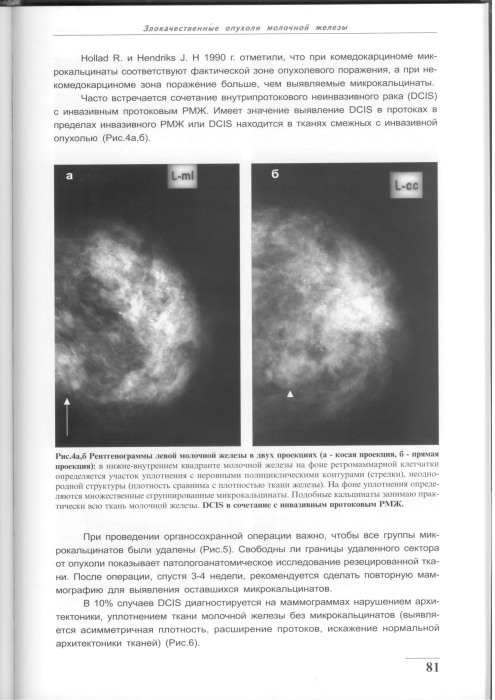

Что такое маммография: важность, процесс и результаты

Раздел: Необычные решения